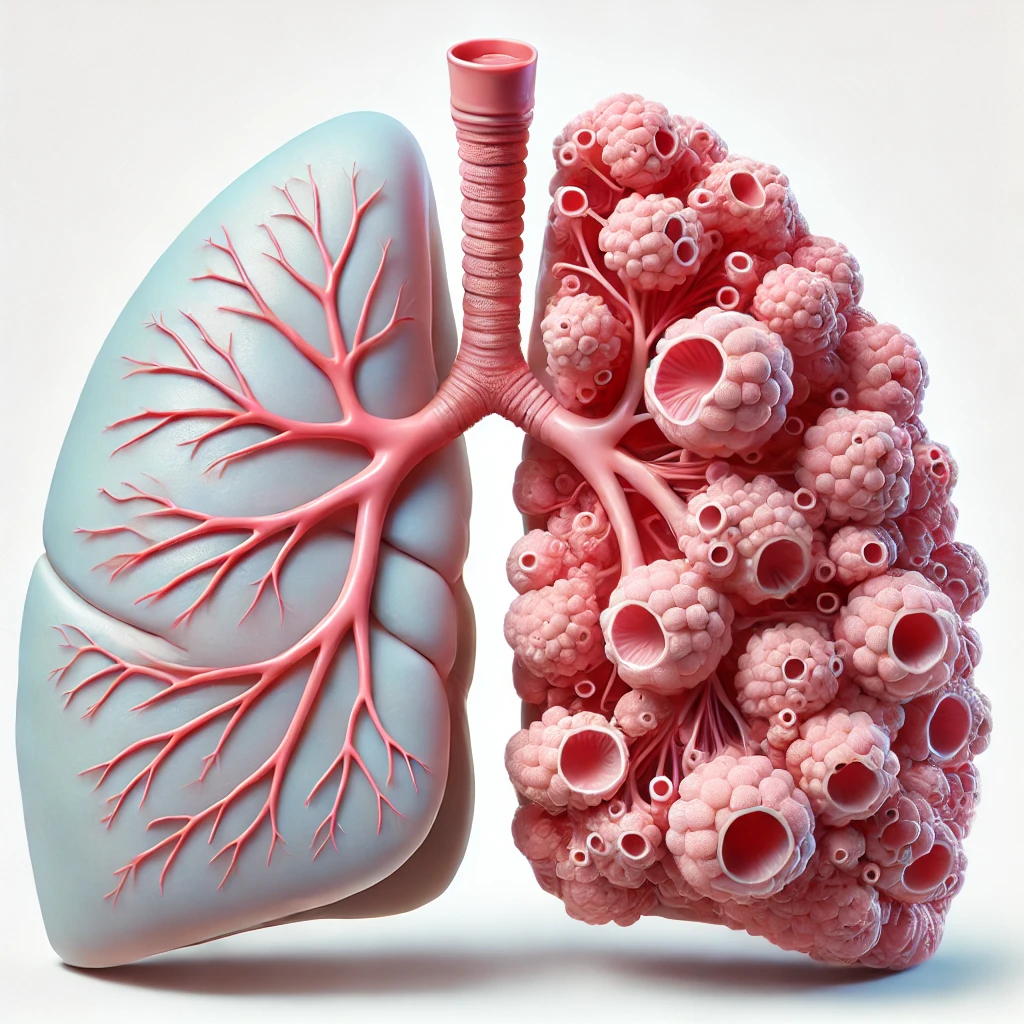

أطباء الأورام والسرطان

50 listings